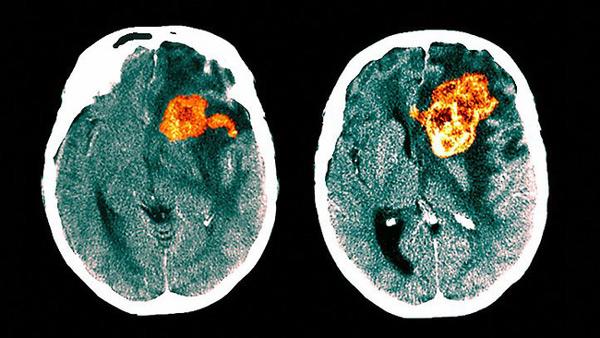

U nguyên bào thần kinh đệm là một loại u tế bào hình sao, xuất phát từ các tế bào hình sao trong bào. Ở người lớn, loại ung thư này thường xuất phát từ đại não – phần lớn nhất của não.

U nguyên bào thần kinh đệm có độ ác tính cao, là một trong những chứng bệnh u não nguy hiểm nhất và thường gặp nhất, Nó được xếp vào mức độ 4, có nghĩa là có tốc độ phát triển và lan truyền rất nhanh. U nguyên bào thần kinh đêm tự có nguồn cấp máu cho riêng nó. Vì vậy nó dễ dàng xâm lấn sang mô não lành, gây chết não dần.